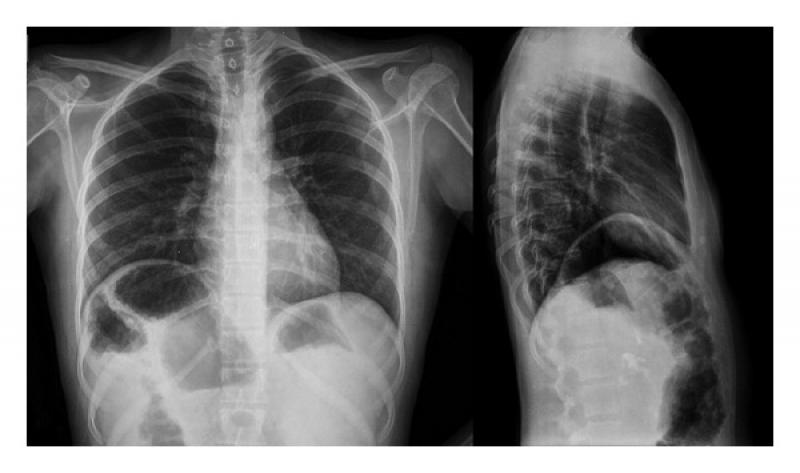

Chilaiditi Sendromu Belirtileri Ve Tedavisi Chilaiditi sendromu, kalın bağırsağın (kolonun) karın duvarı ve diyafram arasında anormal bir şekilde yer değiştirmesiyle karakterize edilen bir durumdur. Bu sendrom, genellikle röntgen veya diğer görüntüleme teknikleri ile tesadüfen tespit edilir. Çoğunlukla asimptomatik olup, bazı durumlarda belirtiler ortaya çıkarabilir. Chilaiditi Sendromunun Belirtileri Chilaiditi sendromu, genellikle belirgin belirtiler göstermeyen bir durumdur. Ancak, bazı bireylerde şu belirtiler görülebilir:

Röntgen, bağırsakların karın duvarı ile diyafram arasında yer aldığını gösterirken, BT taramaları daha ayrıntılı bilgi sağlayabilir. Tedavi Yöntemleri Chilaiditi sendromunun tedavisi, belirtilerin şiddetine ve hastanın durumuna bağlı olarak değişebilir. Tedavi seçenekleri arasında: